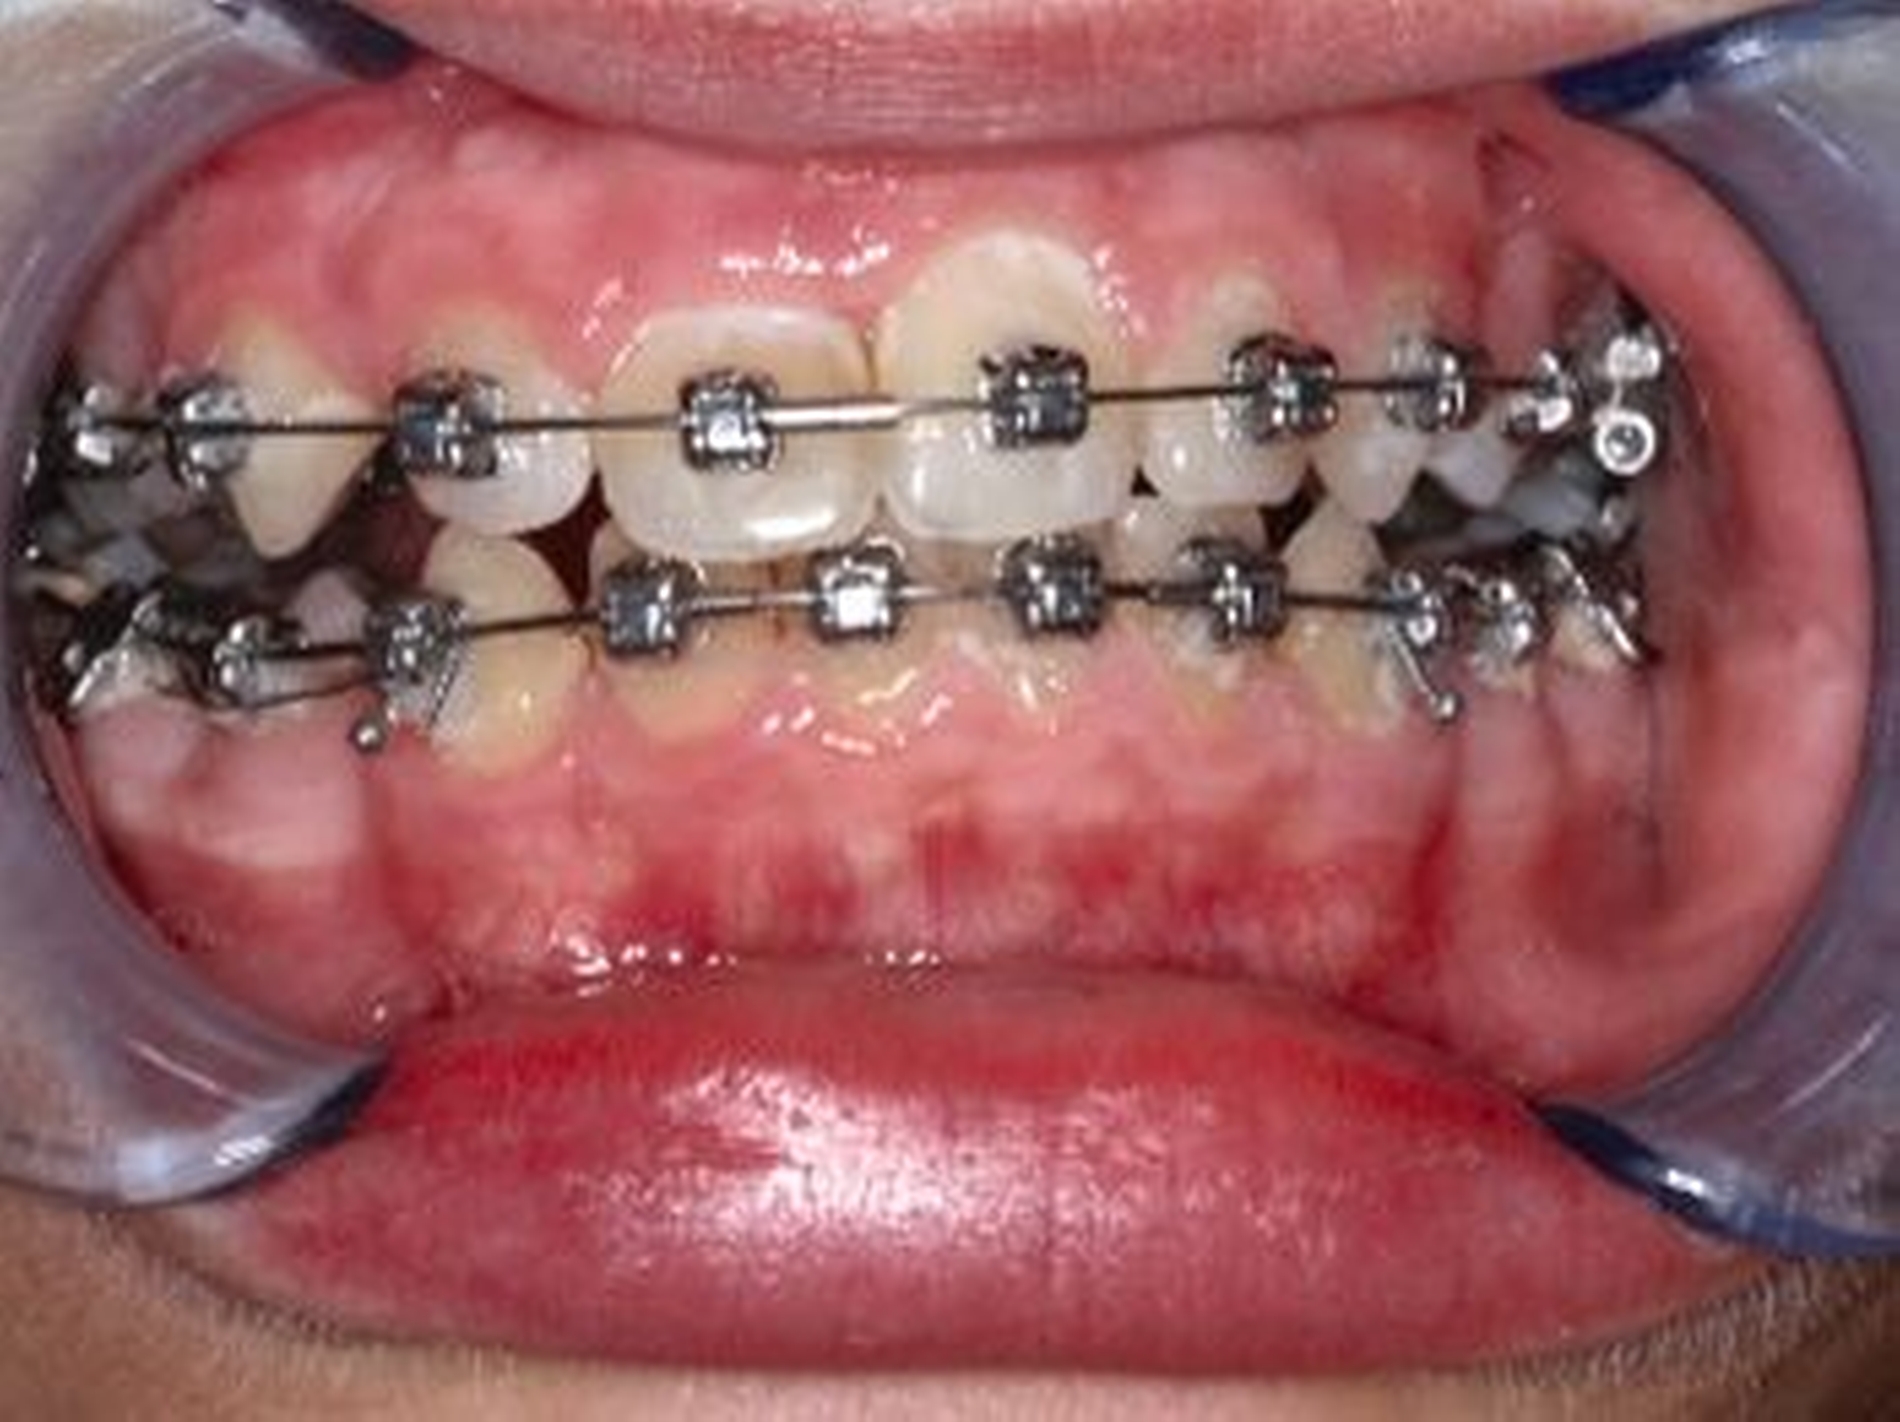

Nach der Einschätzung der Zellvitalität auf der oben genannten Basis folgt die therapeutische Intervention im Sinne der Replantation des betroffenen Zahnes in die gespülte Alveole (vorsichtige Entfernung des Blutkoagulums) mit steriler physiologischer Natriumchloridlösung. Schließlich muss die Replantation schonend erfolgen, da immer mit daran gedacht werden muss, dass es im Rahmen des Traumas zusätzlich zu einer Schädigung des Alveolarknochens gekommen sein kann (Abbildung 1). Diese Schädigung kann eine vollständige oder teilweise Alveolarfortsatzfraktur sein, die entsprechende Beachtung finden sollte. Im Anschluss erfolgt die Schienung des betroffenen Zahnes an den Nachbarzähnen. Dabei sollte ein Zeitraum von ein bis drei Wochen eingeplant werden (Tabelle 1).

Die Replantation sollte langsam und mit wenig Druck erfolgen, um eine zusätzliche Schädigung des Wurzelzements zu vermeiden. Anschließend sollte eine flexible Schienung des Zahnes erfolgen (Empfehlung 50) [Kahler et al., 2016].